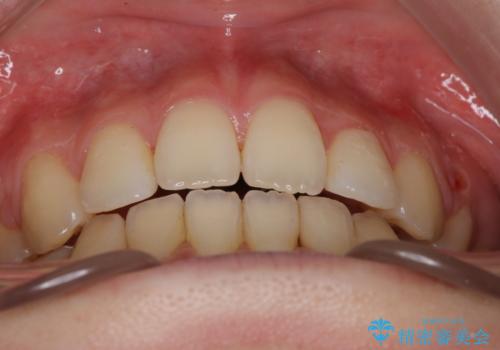

ワイヤーによる抜歯矯正でガタガタの改善

ガタガタも改善しましたが、前歯が内側に引っ込むことにより口元もすっきりして、唇が閉じやすくなりました。